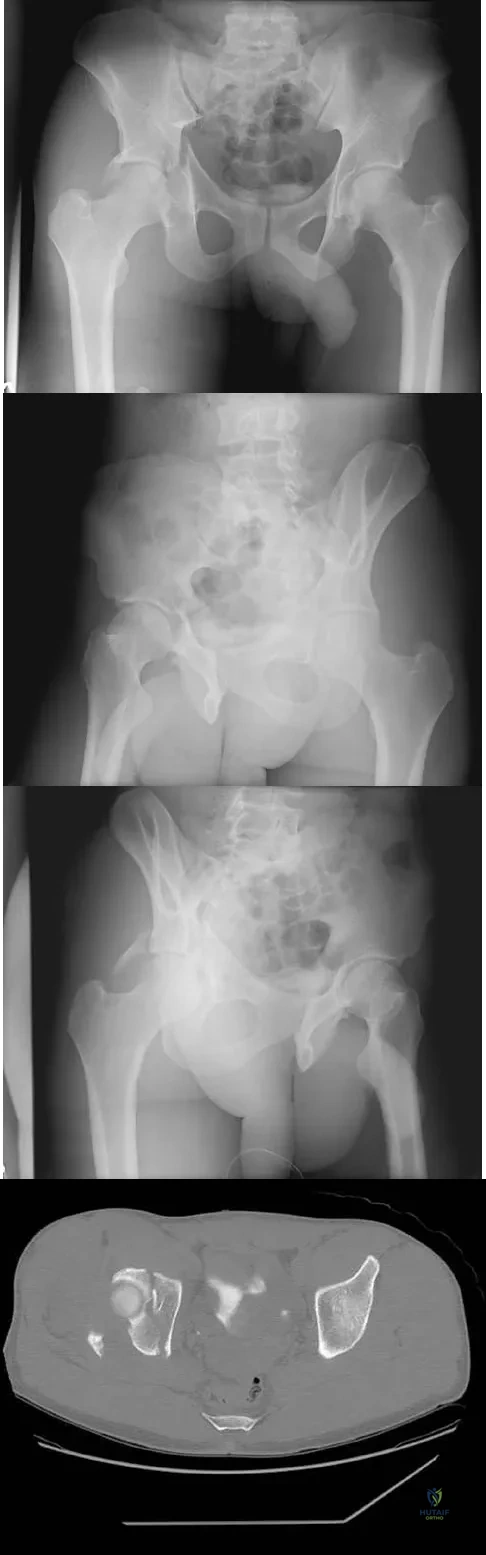

The radiographs and CT scan seen in Figures 28a through 28d reveal what type of acetabular fracture pattern?

Explanation:

The AP, obturator oblique, and iliac oblique views of the pelvis reveal a fracture that disrupts the iliopectineal and ilioischial lines, indicating a fracture that involves both anterior and posterior columns. However, it does not have the other features of anterior or posterior column fracture patterns. A displaced posterior wall fracture is also present, best seen on the obturator oblique view. The anterior to posterior directed fracture line on the CT scan indicates a transverse fracture; therefore, the patient has a transverse with posterior wall fracture pattern. A T-type fracture would be similar but would have a break into the obturator ring. Tile M: Describing the injury: Classification of acetabular fractures, in Tile M, Helfet DL, Kellam JF (eds): Fractures of the Pelvis and Acetabulum, ed 3. Philadelphia, PA, Lippincott Williams & Wilkins, 2003, pp 427-475.